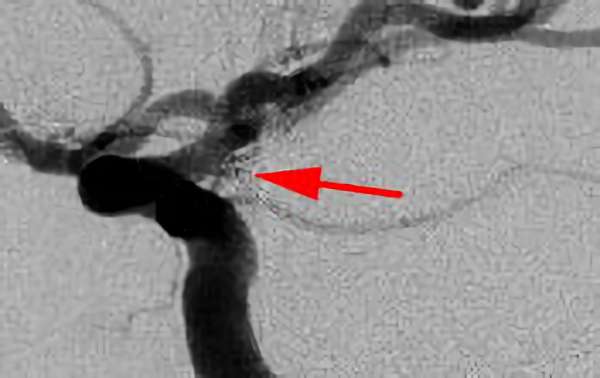

No.1631 手術前

No.1631 手術中

No.1631 手術後